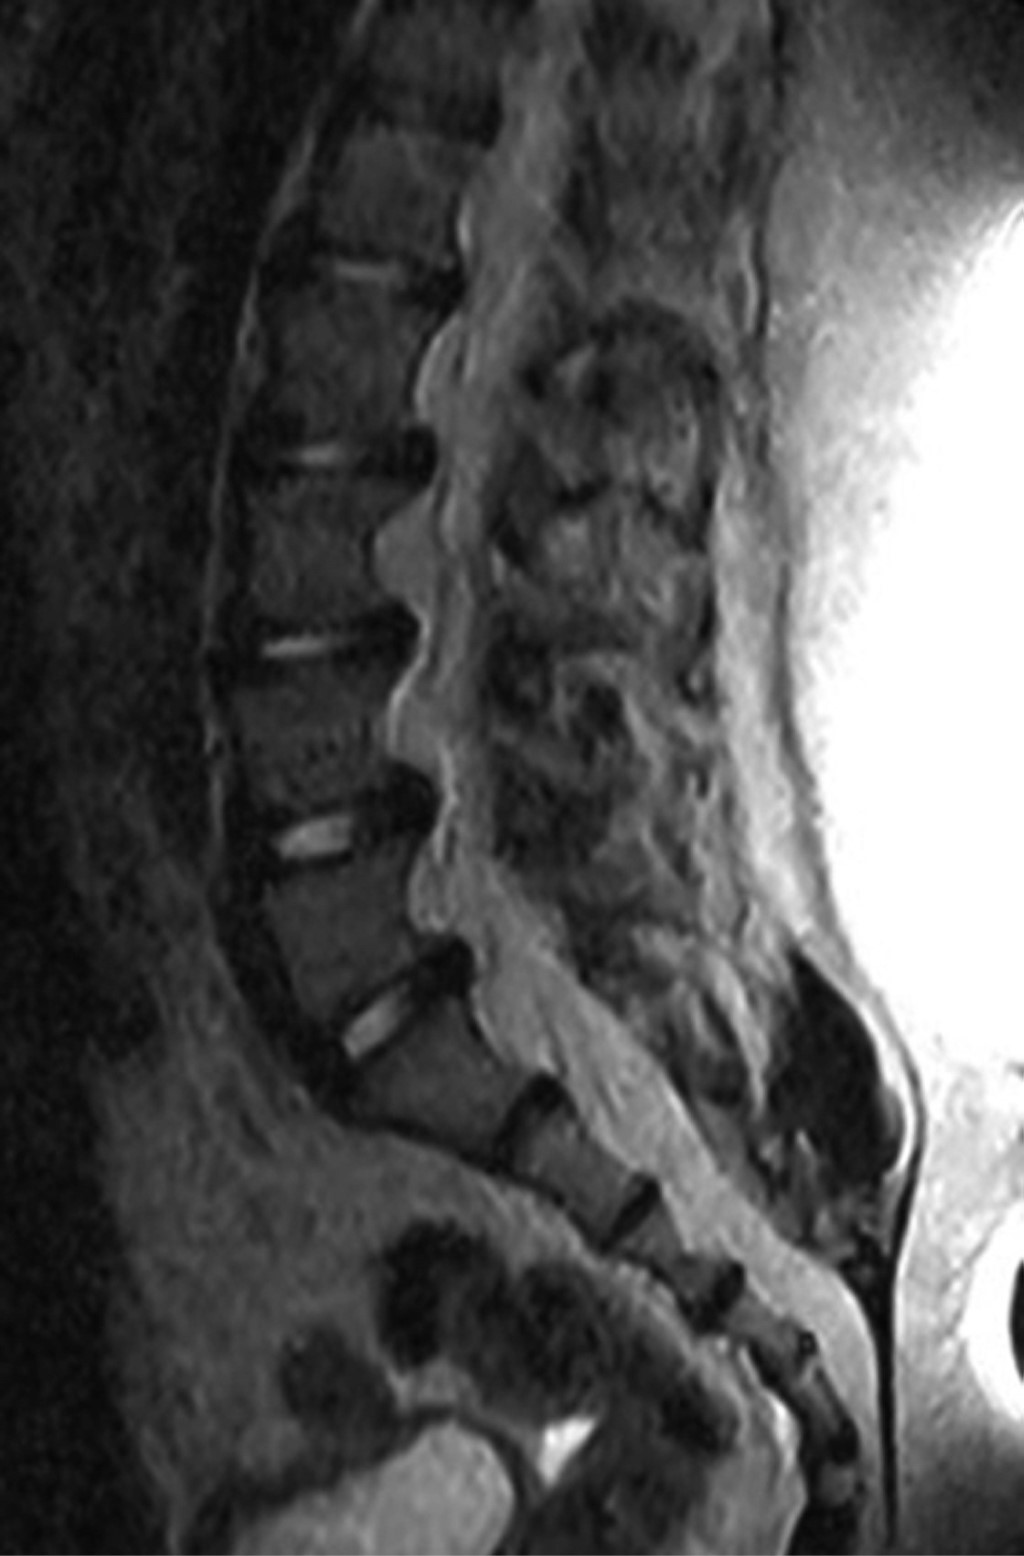

Se realizó, además, una resonancia magnética simple de columna lumbar en la que se reportó una lipomatosis epidural lumbosacra (Figura 8).